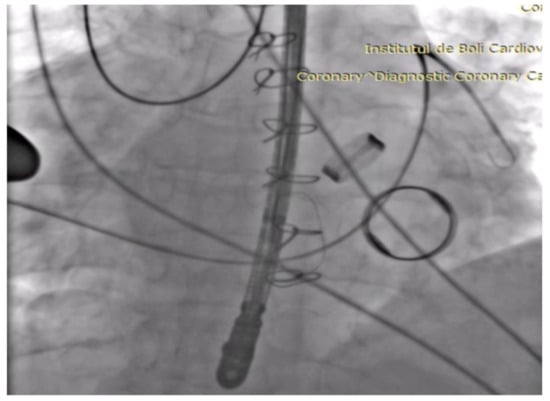

The mean tricuspid transvalvular gradient was 13 mmHg; the peak transvalvular gradient 17 mmHg; peak velocity 2 m/s; PHT (pressure half time) 626 ms; and the tricuspid orifice area 0.4 cm2 (Figure 1). The right atrium was severely dilated with spontaneous contrast inside; bilateral pleural effusion and ascites were also present.

Figure 1. Transoesophageal echocardiography mid-oesophageal four-chamber incidence showing severe tricuspid stenosis with pressure half time (PHT) 626 ms and tricuspid valve area (TVA) 0.4 cm2.